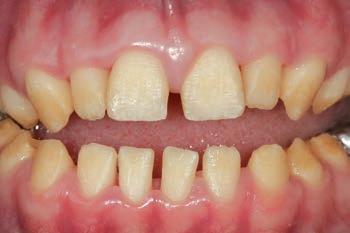

FIGURE 2: Initial treatment focussed on patient-driven improvements in oral hygiene, supplemented by professional mechanical plaque removal and ongoing fourmonthly supportive periodontal therapy. The patient demonstrated a sustained commitment to oral health behaviour change, as evidenced by the establishment of a robust, pale, pink and stable gingival architecture.

Initial management

The initial management of the patient’s oral health focussed on a preventive strategy to address the aetiology of his gingivitis. Non-operative oral health strategies were advised to the patient and a programme of full-mouth professional mechanical plaque removal (PMPR) was completed, while ongoing supportive periodontal therapy (SPT) was implemented on a fourmonthly schedule with a dental hygienist (Figure 2).7,8